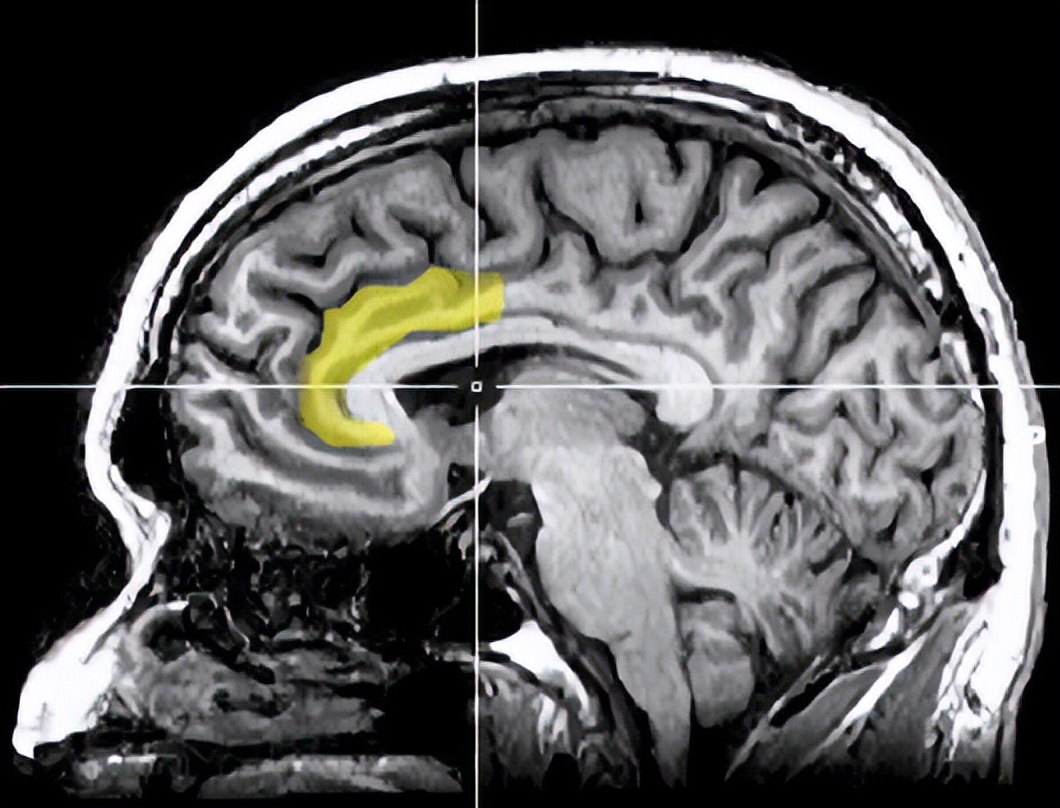

研究人员猜测,当膀胱变得充盈时,相关的神经区域——前扣带皮层(Anterior cingulate cortex)需要发送更强的控制信号来控制膀胱中的尿液无法排出。然而,该区域负责的其他任务(例如注意力分配、奖励、决策、冲动控制)也会受到抑制信号的溢出效应。

黄色高亮部分即为前扣带皮层 图源wiki